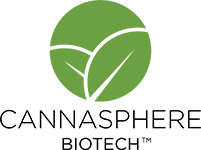

A liposome is a spherical vesicle resembling a cell with an outer shell comprised of fat-soluble phospholipids that protect the water and fat-soluble actives inside from degradation while en route to their destination. Since these phospholipids are bioidentical to our cell membranes, this outer “shell” functions the same way a human cell membrane does to protect its molecular center and inner compartments.

One of the most important functions of phospholipids is to protect and regulate the transport of nutrients through the small intestine and into the blood stream targeting your cells. In this capacity, these molecules work as ‘gatekeepers’ and play an integral role in determining what goes in and out of the cell.

How does nanoliposomal delivery supercharge bioavailability?

The key to nanoliposomal delivery is in the protective layer of the nanoliposome’s phospholipids. First, it is important to understand the structure of phospholipids, as this holds the key to grasping how nanoliposomes work.

In layman’s terms, each phospholipid molecule is made up of a circular “head” which likes water and a “tail” that does not. The heads are attracted to water while the tails try to avoid it, causing the phospholipids to arrange themselves in double layered lines where the heads are all outside, touching water, and the tails are “dry” in the encasement they’ve created.

In an aqueous solution (i.e. water), the phospholipids automatically self-assemble into a double layer so the hydrophobic fatty acid tails (which like to stay dry) move away from water and turn inward; whereas the water-loving phosphate head moves toward the liquid by turning toward the middle of the double layer. This results in a closed, spherical structure called a “nanoliposome” with a hollow aqueous core surrounded by a double-layer (bi-layer) membrane, which encapsulates active CBD and other nutrients into these microscopic vesicles and protects them from digestive degradation and hydrolysis in the bloodstream until they are fused into the cells.

- Enable fusion of active nutrients through membranes of targeted cells at the molecular level